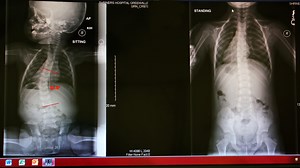

Body Cast - Scoliosis

FBC - Kyphosis